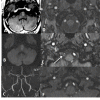

Fig. (12)

Axial Flair (A) and DWI (B) show different ages of thromboembolic infarctions in the brain stem and right cerebellum. Focal narrowing of right VA is seen on a MIP image of brain MRA (C). Source images of 3D TOF MRA from caudal to cranial (D-F) show eccentric luminal narrowing associated with increased external diameter of right VA due to intramural hematoma which is seen minimally hyperintense on E (arrow).